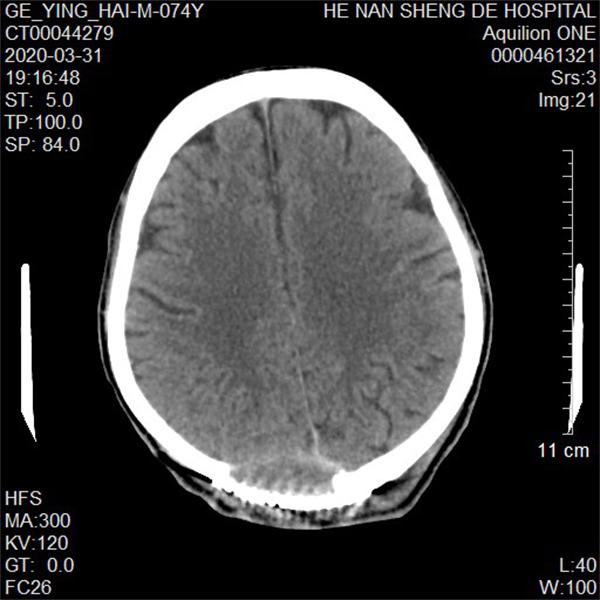

术后复查CT影像结果视图